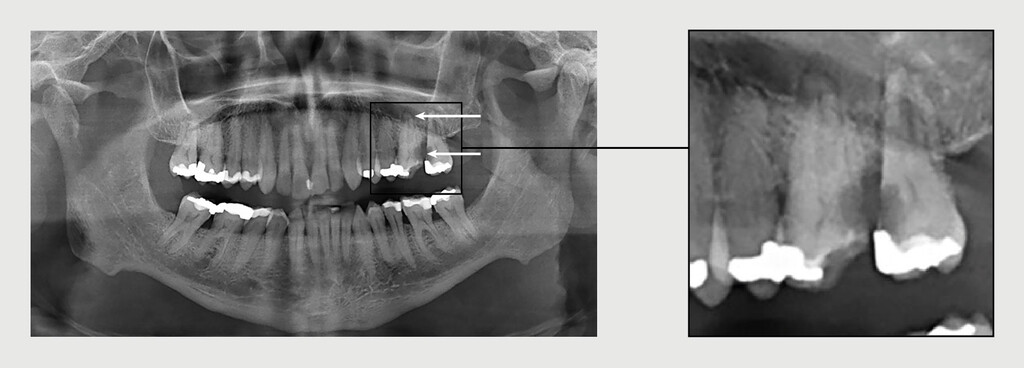

Orthopantomogram

Figuur 3 | Orthopantomogram

Orthopantomogram van de patiënt. Er is een duidelijke cariës profunda te zien van gebitselementen 26 en 27 (onderste pijl). Tevens is er een radiolucente afwijking zichtbaar rond de wortelpunt van elementen 26 en 27 (bovenste pijl).